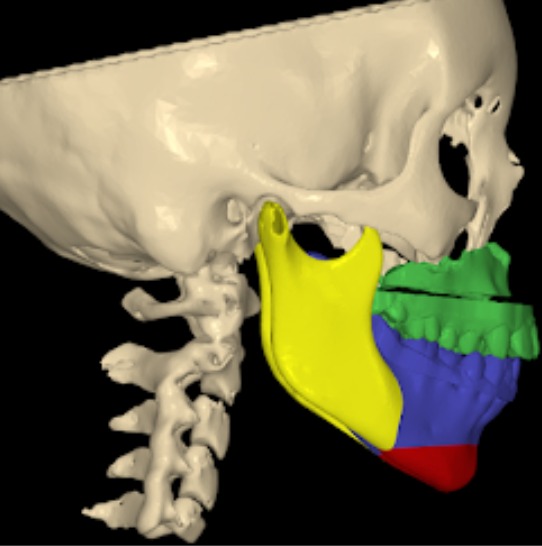

Maxillary hypoplasia is a condition characterized by the underdevelopment of the upper jaw (maxilla), which can affect both facial appearance and oral function. It often results in a sunken midface, improper bite alignment, and may contribute to breathing or speech difficulties. This condition can be congenital or develop during growth, impacting overall facial harmony and balance.

- Pre-surgical Orthodontics: Often needed before the actual surgery takes place. Imaging: X-rays and CT scans are required.

- Planning: Virtual surgical planning is performed on a computer, along with model surgery.